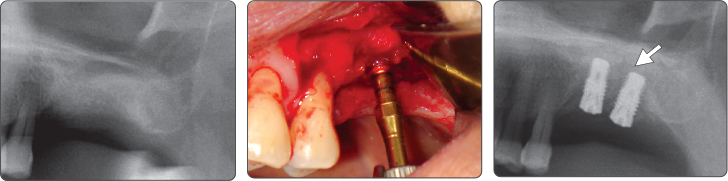

1. Elevación de seno (Implante Ø4.0)

2. Elevación de seno (Implante Ø5.0)